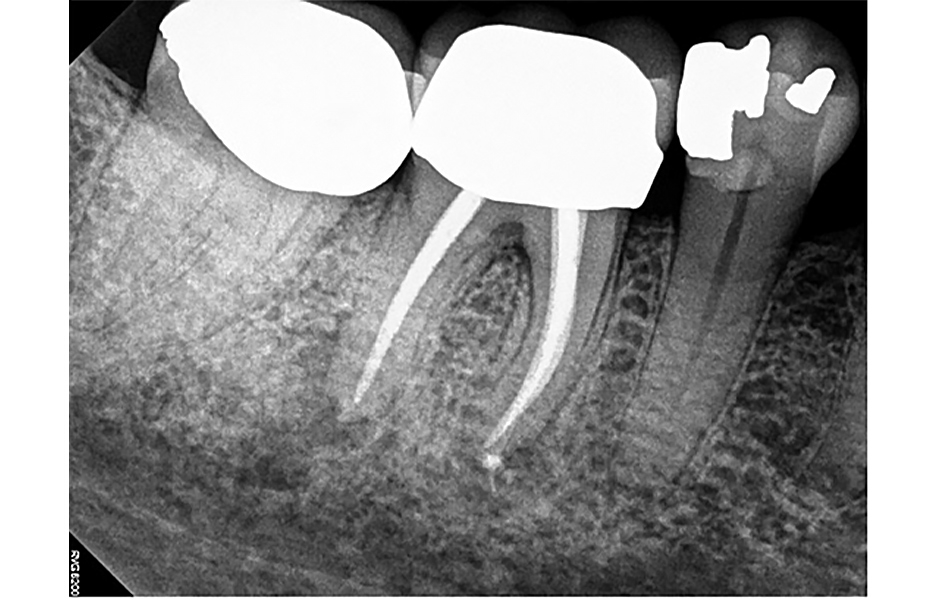

Byl pořízen pooperační periapikální rentgenový snímek (obr. 3) a pacientce byly poskytnuty instrukce pro domácí péči. Následující den byla pacientka telefonicky kontaktována, zda nemá nějaké otázky či obavy. Uvedla, že se cítí dobře, ale pociťuje mírnou citlivost a jednou užila ibuprofen.

Obr. 3: Pooperační periapikální rentgenový snímek zubu 46 bezprostředně po reendodontickém ošetření v červnu 2022.